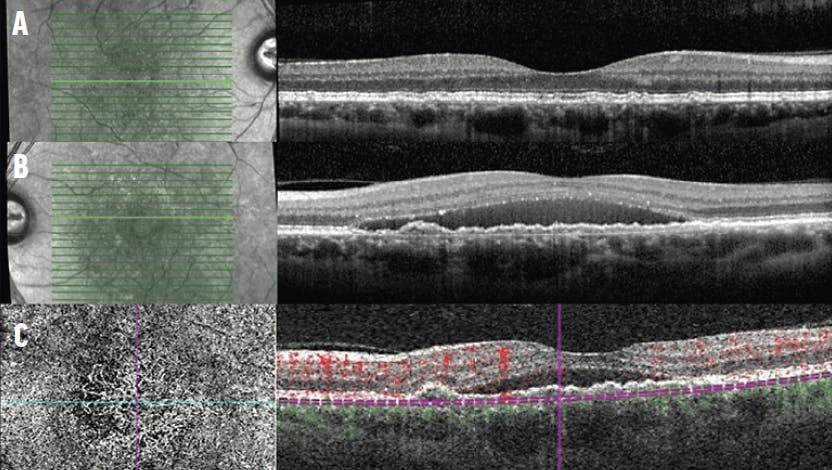

Case No. 2: A 60-year-old White woman was referred for bilateral intermediate AMD. The fundus examination demonstrated intermediate drusen in each eye with pigment changes in the left eye and no hemorrhage. The foveal cross-sectional OCT of the right eye demonstrated small drusenoid PEDs (Figure 4A). The left eye demonstrated SRF in excess of what would be expected for wet AMD and a confluent row of PEDs forming a double-layer sign (Figure 4B). OCTA demonstrated type 1 neovascularization along the nasal margin of the PED (Figure 4C).

<p>Figure 4. OCT of the right (A) and left (B) eyes showed intermediate AMD of the right eye and CSCR with indolent secondary type 1 neovascularization of the left eye superimposed on intermediate AMD. OCTA with an en-face flow image using a slab with boundaries between the RPE and Bruch membrane demonstrated a type 1 neovascularization along the nasal margin of the PED (C).</p>

Figure 4. OCT of the right (A) and left (B) eyes showed intermediate AMD of the right eye and CSCR with indolent secondary type 1 neovascularization of the left eye superimposed on intermediate AMD. OCTA with an en-face flow image using a slab with boundaries between the RPE and Bruch membrane demonstrated a type 1 neovascularization along the nasal margin of the PED (C).